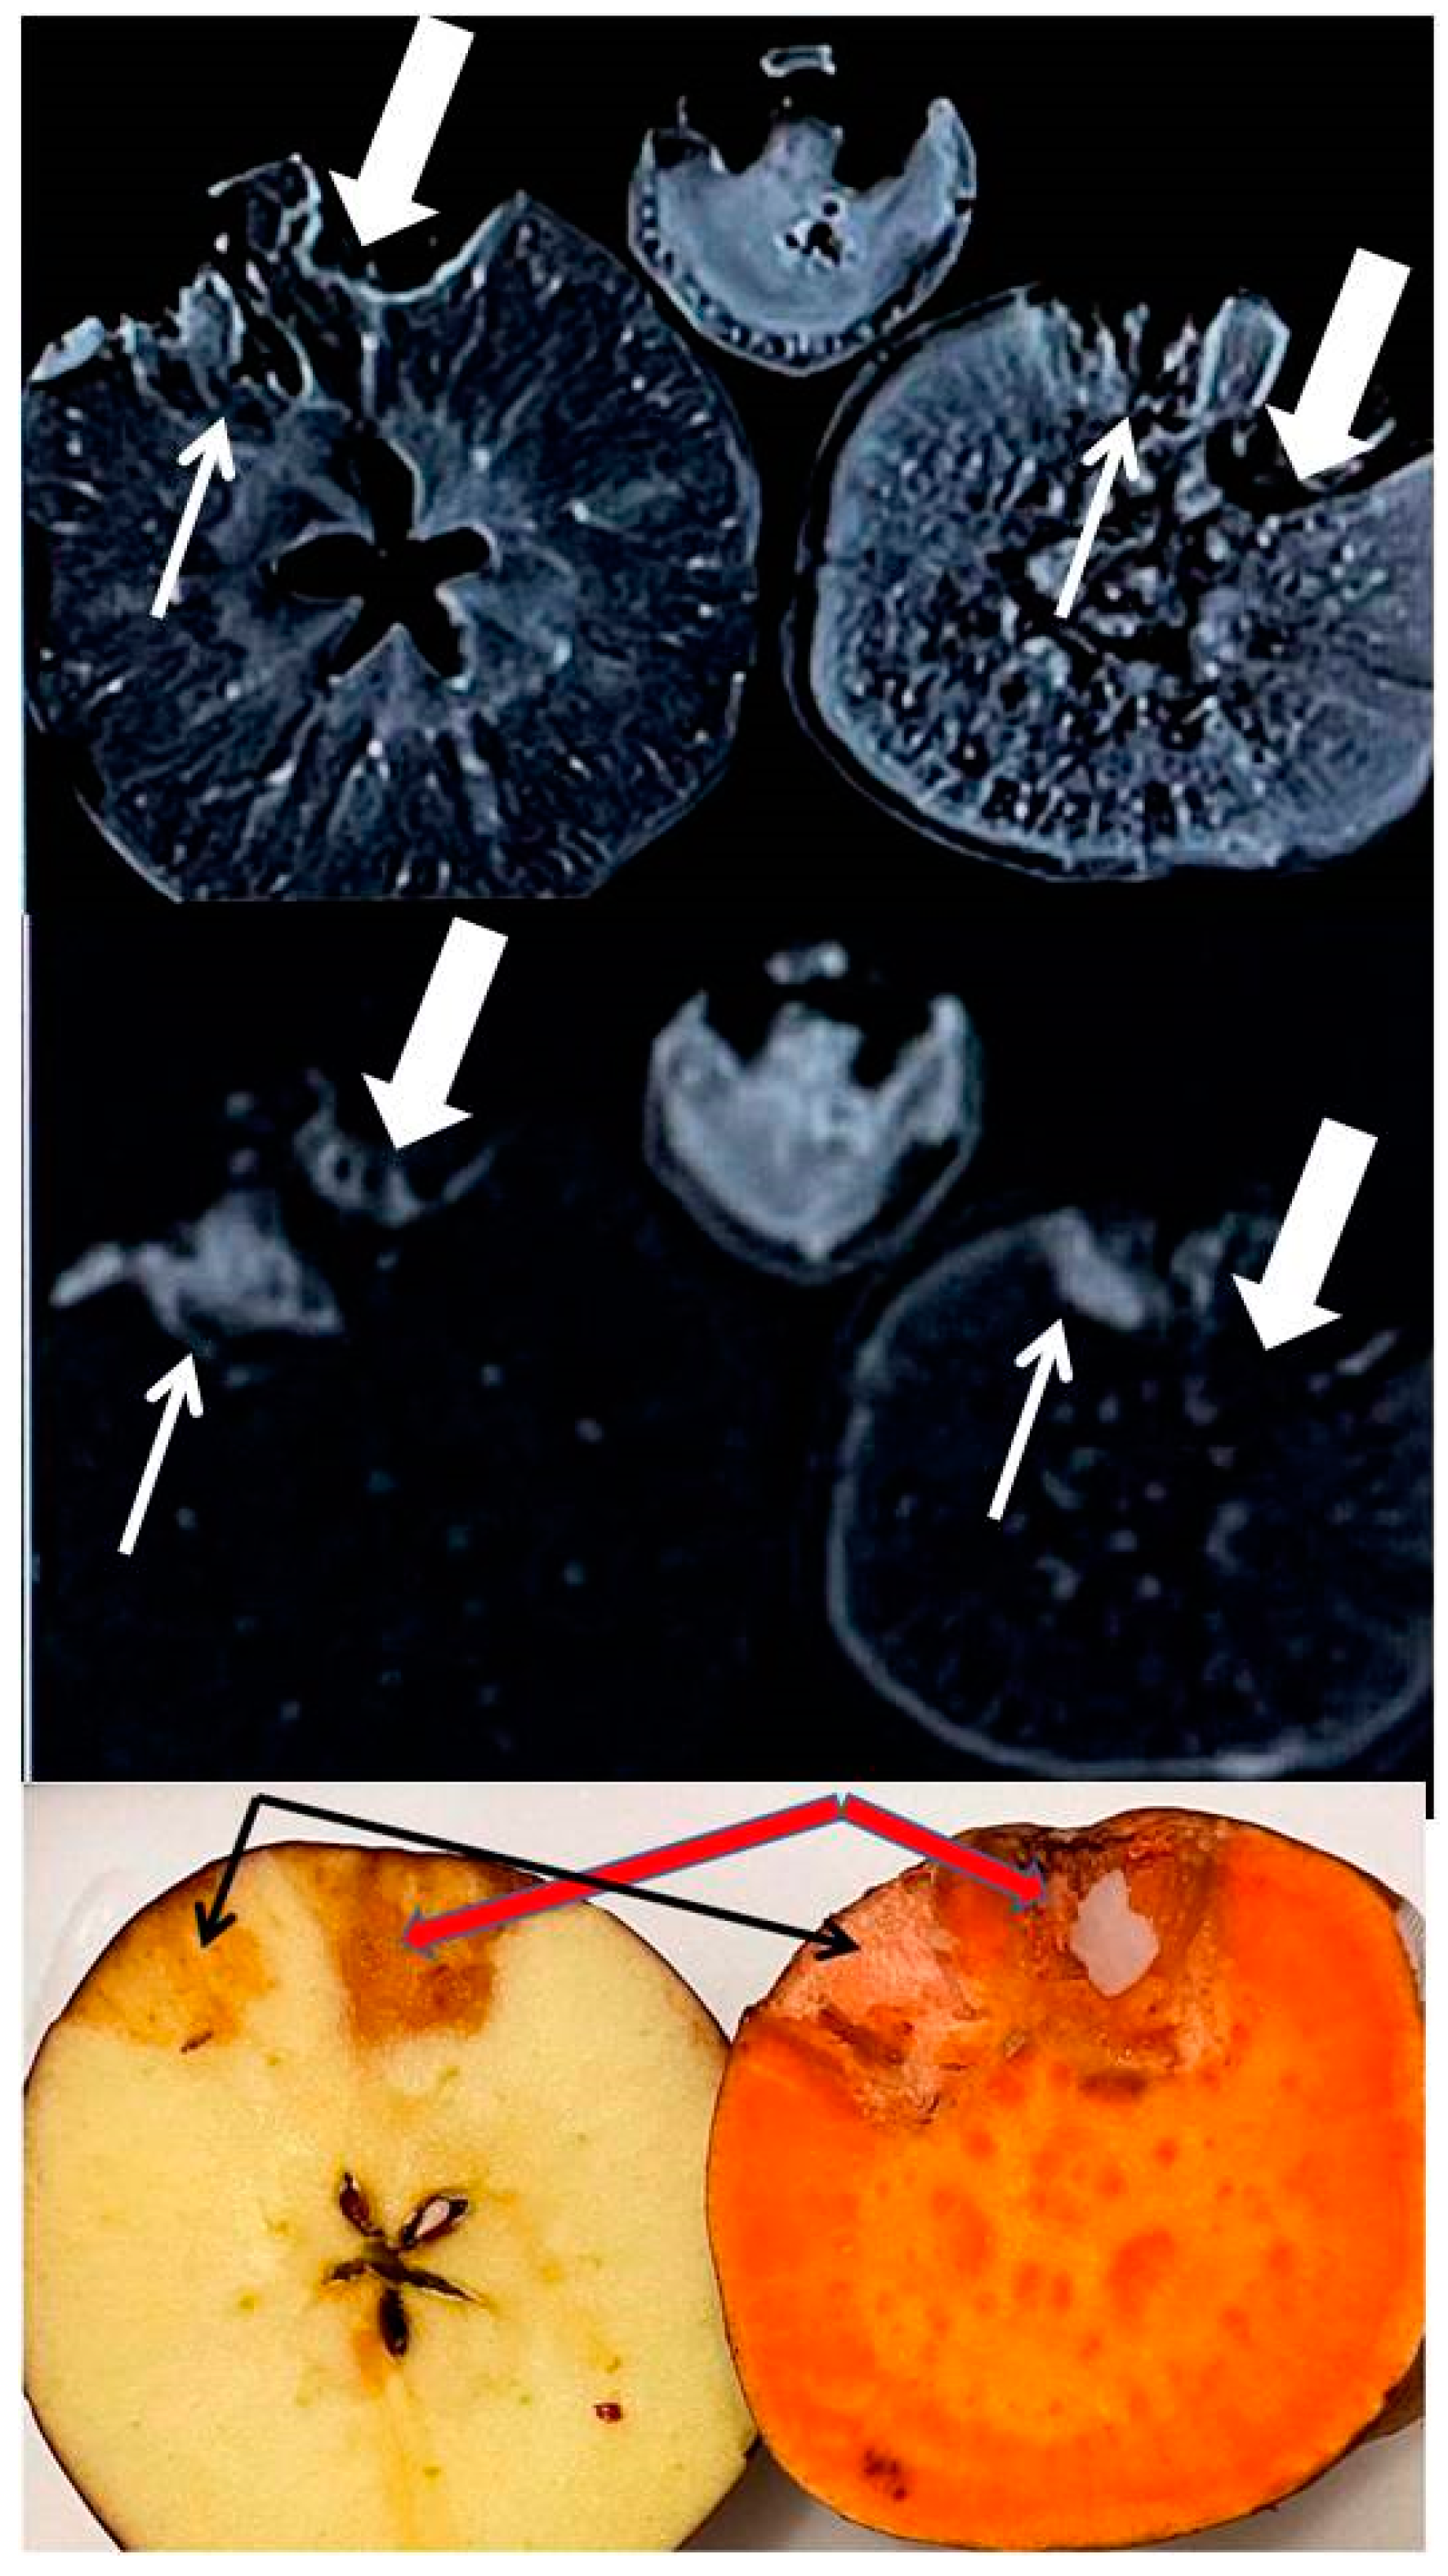

3.4. MR Imaging

In the left panel of Figure 3, the T1-weighted images (top two rows, prior to and immediately after Gadavist and Iohexol addition) show large signal voids in the left, within and adjacent to the Gadavist added wells while on the right, the Iohexol added wells and surrounding bulk matrix show hyper intense signals in both samples. This is better visualized in the (post-pre) contrast subtraction images (bottom three rows, Figure 3).

Figure 3.

MR images of the mineral-rich model fruits and vegetables. First row: Pre-contrast MR image at 1.5T Siemens system, apple (left) and sweet potato (right). Manually carved wells (2 × 2 × 10 mm3 or 0.04 mL volume) are shown (white arrows). Second row: Post-contrast MR image when Gadavist is added at the left wells and Iohexol in the right wells for both fruits. Notice signal loss due to paramagnetic nature of Gd3+ and enhanced signal due to Iohexol. Third to fifth rows: Time series subtraction images (post-pre contrast) at time = 5 min, 35 min and 65 min are shown. More pronounced enhancement is seen with Iohexol in sweet potato.

The signal voids are due to T2* shortening of bulk protons by strongly paramagnetic Gd3+ in the infused Gadavist. The continued signal enhancement in the carbohydrate protons surrounding the right wells with time are presumably due to a chelation process by Iohexol complexes for extracting paramagnetic metals from the biochemical pathways within both samples. Potential chelated paramagnetic candidates that can induce T1 shortening of bulk protons are Fe2+ and Mn2+ in both systems

The iodine added MRI image was acquired five days post iodinated contrast addition, while contrast was allowed to be absorbed in the walls of the taped wells (generally took a few hours for absorption). Five days post images shows the stable, residual distribution of minerals released by the bulk matrix in response to iodine induced chelation, with no MRI contrast involved. With T1 and T2 both being bright in these images, one may suspect the accumulation of weakly paramagnetic species in the walls (originating from endogenous pool) that have caused T1 shortening and T2 lengthening of bulk protons. These are suspected to be low concentrations of Fe and/or Mn species chelated by iodinated media.

Top row: T1-weighted image (parameters in the text) showing rim enhancement of residual iodinated species presumably containing a paramagnetic substance that lowered the T1 relaxation times for both wells of both fruits. This also shows multiple focal and diffuse regions of such paramagnetic species distribution at the interior of the fruits that should be Fe ions which were probably removed from biochemical reservoirs and that are present in Fe2+ or Fe3+ forms.

Middle row: T2-weighted image (parameters in the Methods section) showing high signal from long T2 species near the wells and almost total signal loss from short T2 species at the interior for both of the fruits. Such paramagnetic effects seem to suggest iron chelation by iodinated agents.

Bottom row: After MRI, the fruits were cut open, and the bottom row shows an optical photograph of a residual iodine stain in the surrounding matrix of the wells. The wells were fully dry with no fluid trapped or any sign of degradation since iodine kills bacteria. Omnipaque 350 shows darker stains, thick arrow (350 mg/mL of iodine present as opposed to 240 mg/mL in Omnipaque 240, thin arrow).